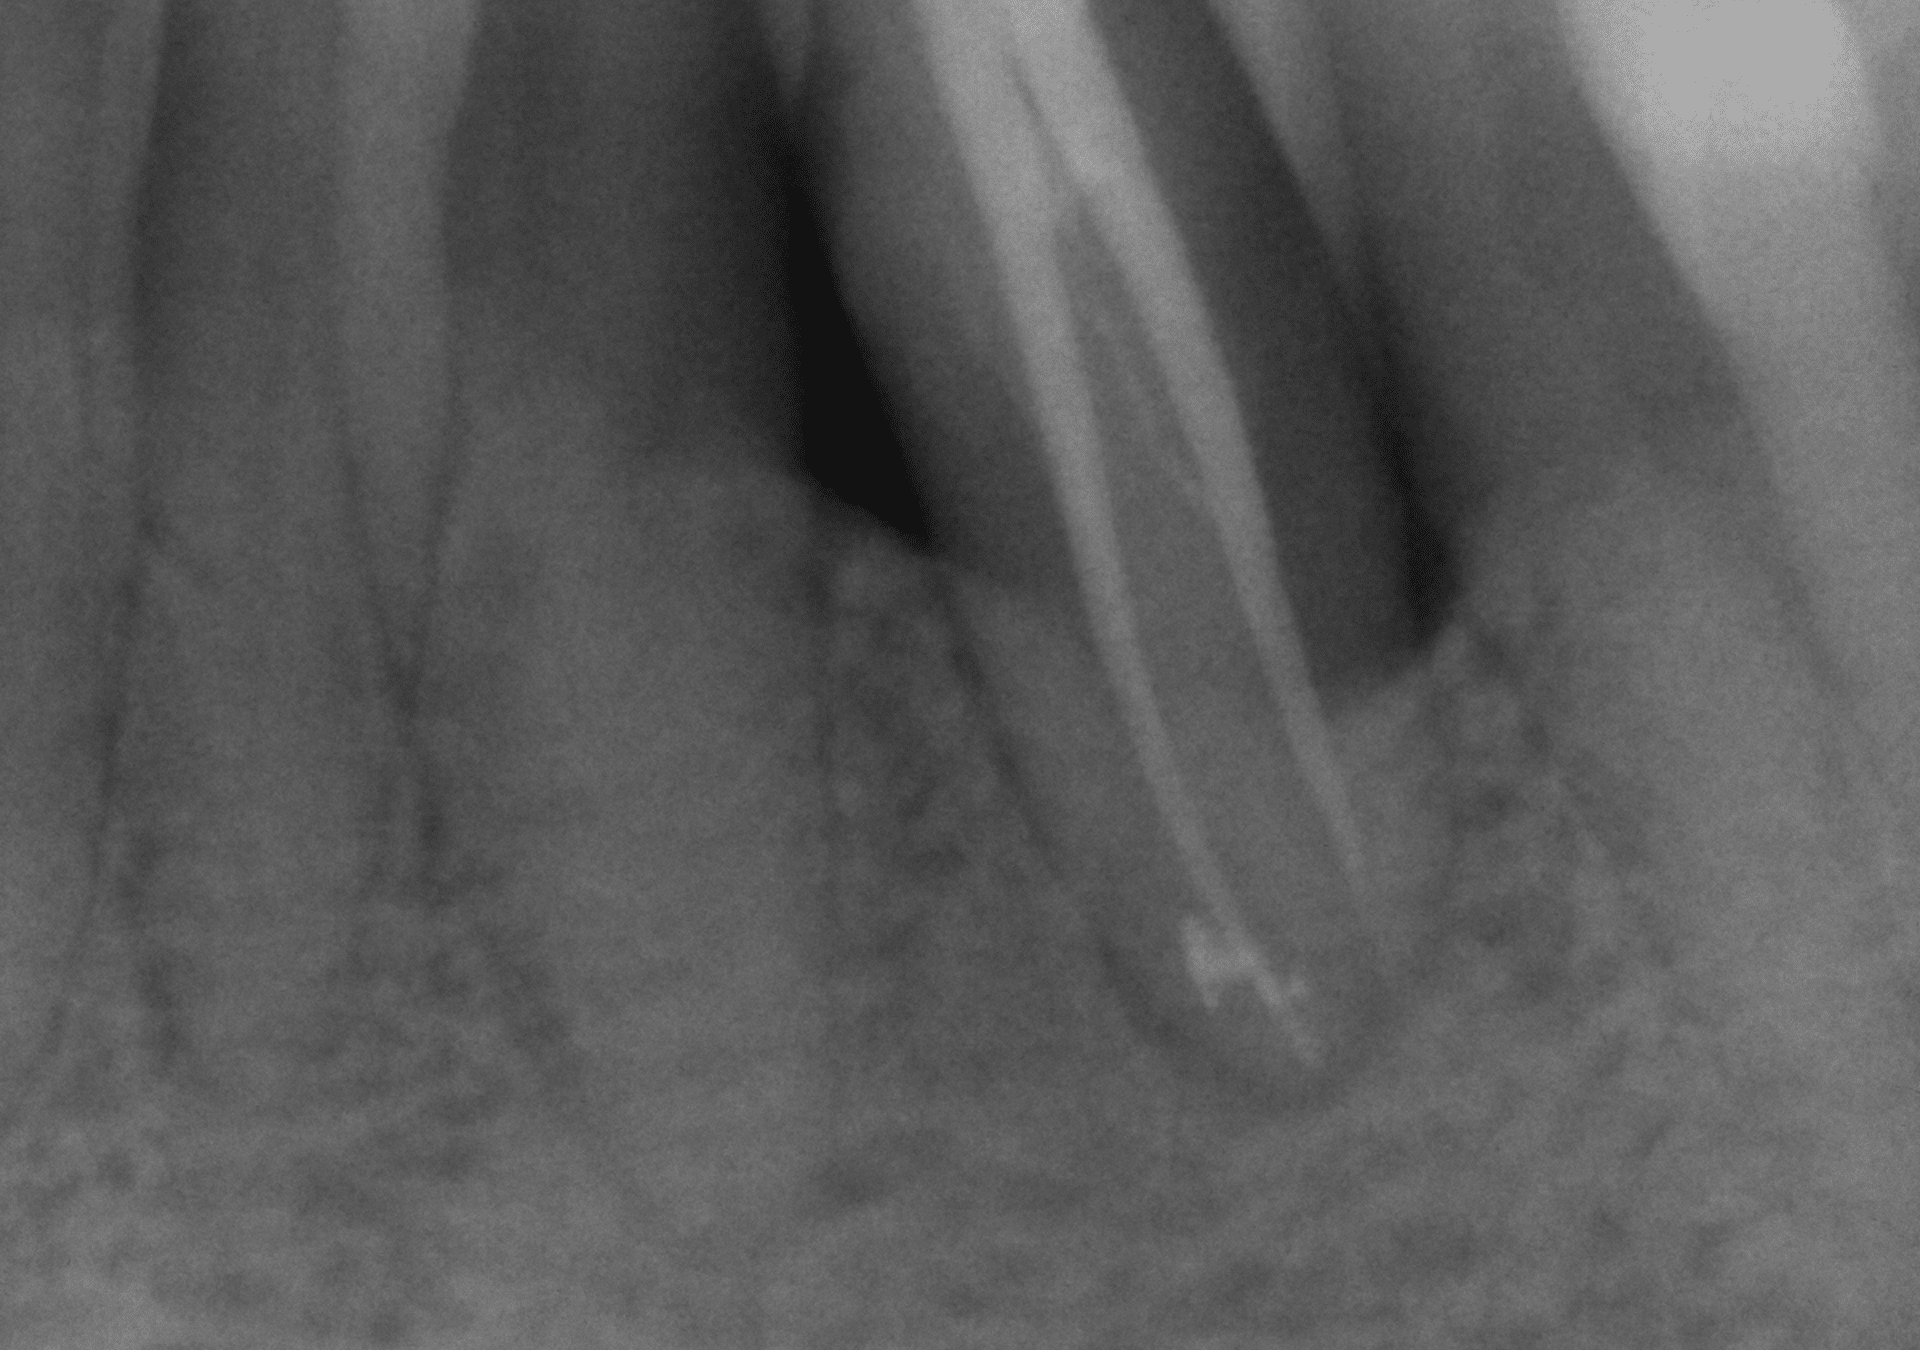

Endodoncia

- Amplia experiencia en tratamientos de endodoncia para resolver casos de alta dificultad.

- Diagnóstico y seguimiento con CBCT para analizar con exactitud los casos evaluados.